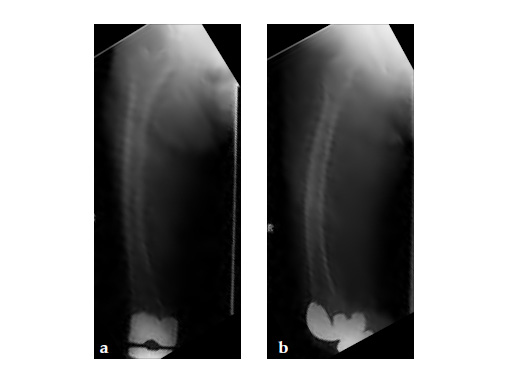

No edema indicated a stress fracture (see Fig 4a-b).

Based on the negative MRI thigh and positive MRI lumbar spine of multiple levels of spinal stenosis, the patient underwent epidural analgesic injection. Patient sustained right femur midshaft periprosthetic fracture the next day after her epidural injection with no trauma.

Notice the fracture decrease the emphasis on the anterolateral bow of the femur (See Fig 5a-b).